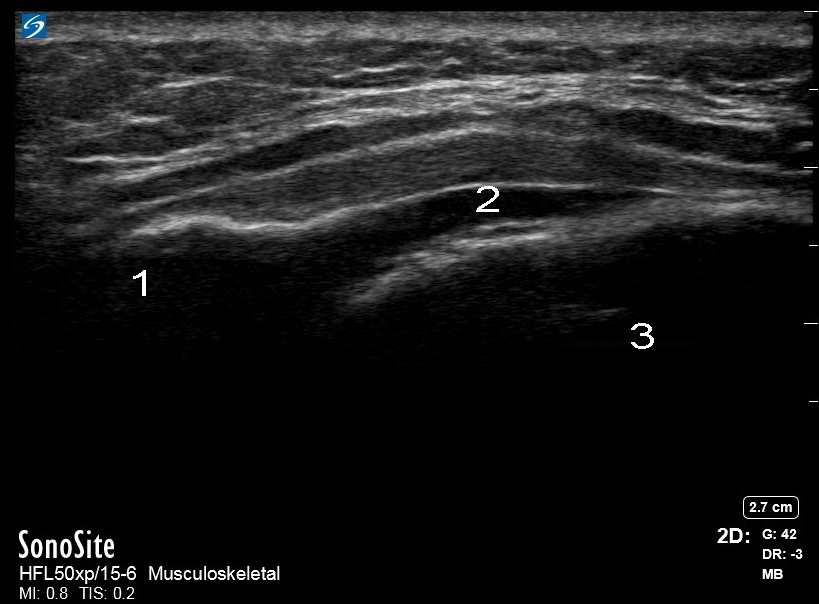

脊椎靱帯仙画像

脊椎仙骨硬膜外解剖学

後部板

裂孔

前歯部板